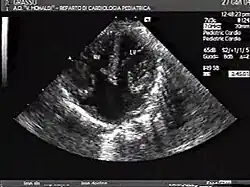

The proper development of the atrioventricular canal into its prospective components (The heart septum and associated valves) to create a clear division between the four compartments of the heart and ensure proper blood movement through the heart, are essential for proper heart function. When this process does not happen correctly, a child will develop atrioventricular canal defect which occurs in 2 out of every 10,000 births.[1] It also has a correlation with Down syndrome because 20% of children with Down syndrome have atrioventricular canal disease as well. This is a very serious condition and surgery is necessary within the first six months of life for a child.[2] Half of the children who are untreated with this condition die during their first year due to heart failure or pneumonia.[3]

Atrioventricular canal defect is a combination of abnormalities of the heart and is present at birth. There is a problem when there are holes present in the walls that separate chambers (septa), as well as when valves are incorrectly constructed. There are other names for these heart abnormalities such as endocardial cushion defects or atrioventricular septal defect.[4]

Atrioventricular canal defect may be divided into partial or complete forms. In the partial form, openings between the left and right atria and improper formation of the mitral valve exist. In the complete form, there is free movement in all chambers because there is a large hole where the atria and ventricles meet, and instead of there being two valves there is one common valve.[4]